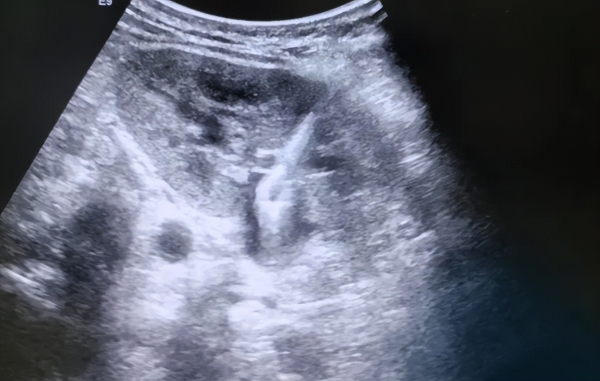

一开始肠胃确实轻松了不少,排便更规律了,人也精神了。但三年后的一次单位体检,他做完腹部B超,医生眉头一皱,紧接着叫来了全科室的医生来"参观"他的B超图像。

图像显示:他的肠道里堆积了大量未消化完全的纤维团块,形成了多个"假性结节",甚至出现了轻微的脂肪肝和肠壁变厚。

医生说:"不是病情罕见,而是吃法特别。"红薯虽好,但他这种长期、单一、无搭配的吃法,让肠道长期处于高膳食纤维负荷状态,不仅吸收效率下降,还增加了胃肠负担。